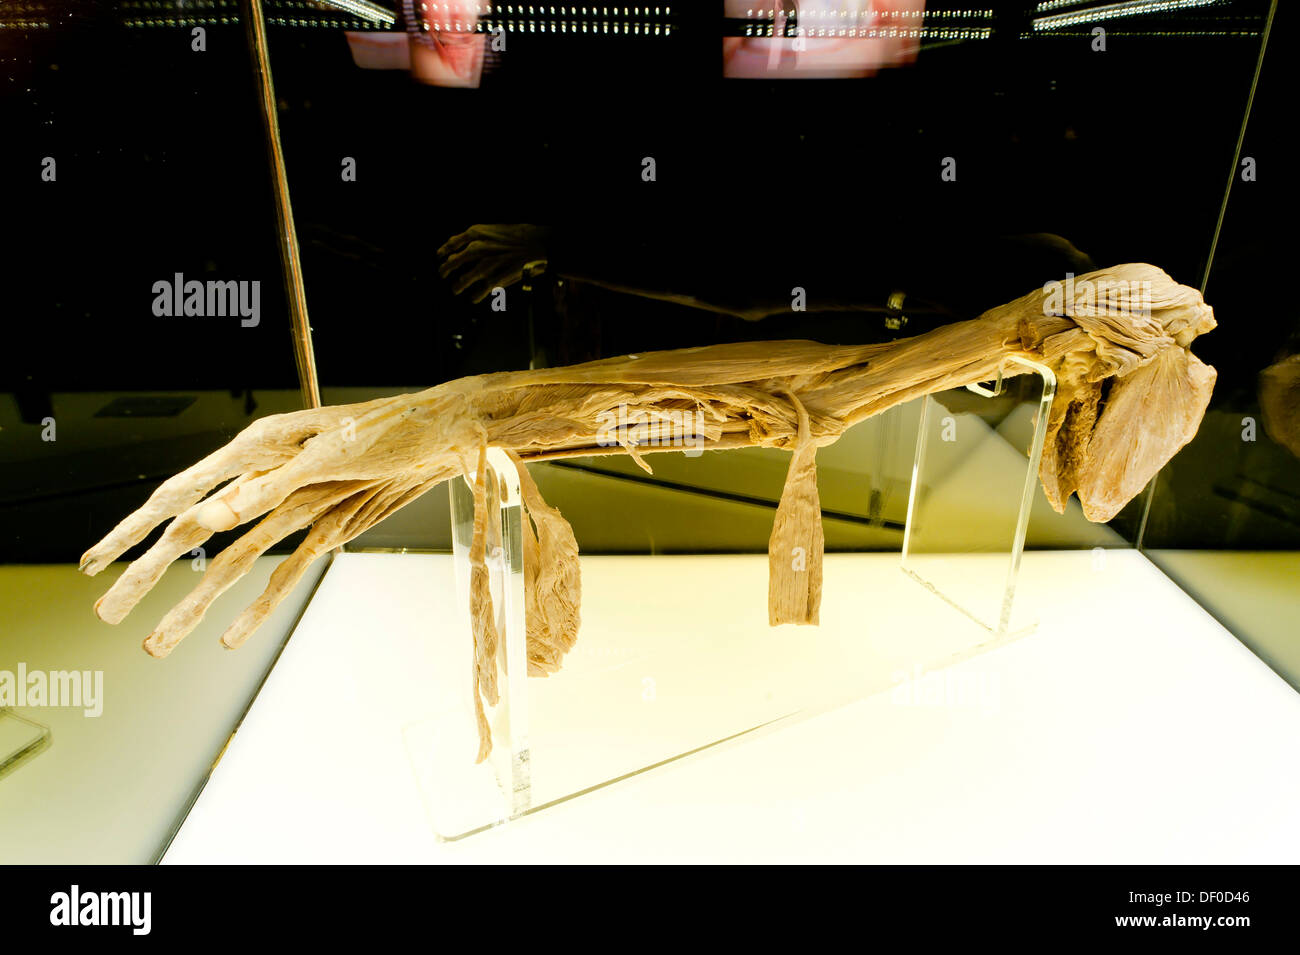

Upper limb Stockfotos & Bilder